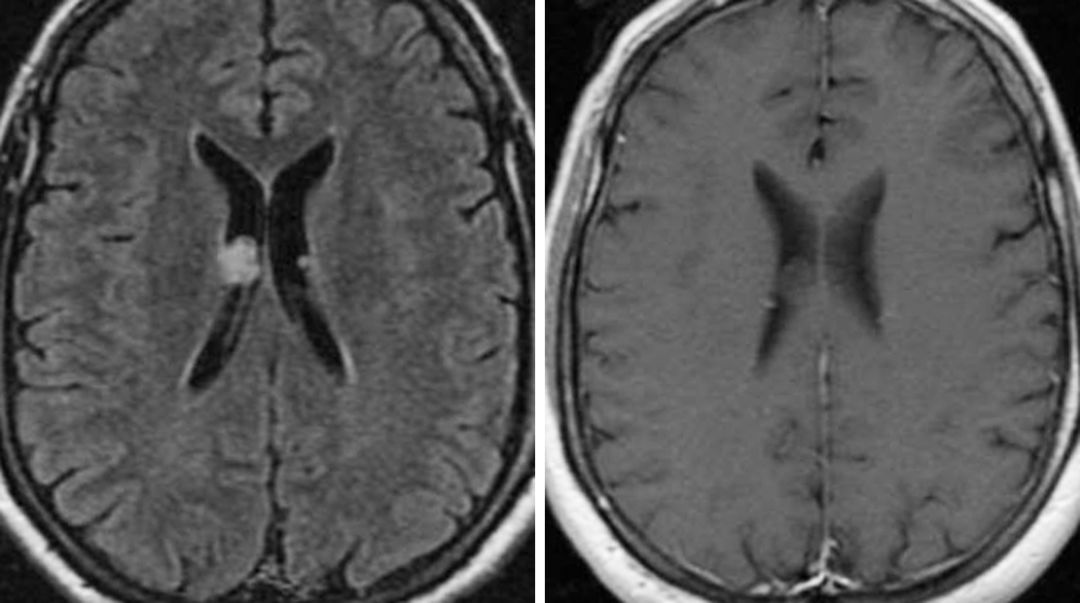

图1. 脑室内小结节状室管膜下瘤,在FLAIR加权相上呈高信号(左),是一种少见的良性肿瘤。增强后有多种表现,这例在T1增强加权相后无明显强化(右)。